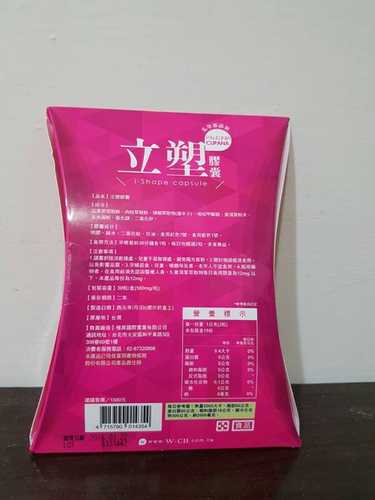

每一盒Supercut塑魔纖立塑膠囊都有三小包,每一小包有10顆膠囊

Supercut塑魔纖立塑膠囊的成分有:瓜拿那萃取粉、肉桂萃取粉、辣椒萃取物(唐辛子)、吡啶甲酸鉻、番瀉葉粉末、玉米澱粉、氧化鎂、二氧化矽。

之前上過相關課程,成分表是依照每項成分的多寡來排列順序,排在最前面的就是產品的主要成分!

食用方式:早晚餐前30分鐘各1粒,每日不超過2粒。(多食無益)

番瀉葉萃取物每日食用限量為12mg以下,